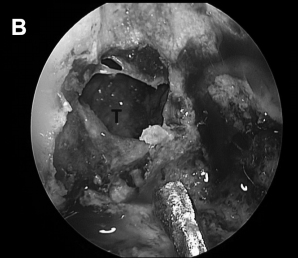

▼术后 (C、D) 图像显示病灶次全切除,并显示鼻中隔瓣修复良好。显示岩尖最后面的小部分残留病灶(C、D、箭头)。值得注意的是,除了鼻中隔后三分之二和蝶窦外,所有其他鼻内正常组织结构均被保留完整无损。